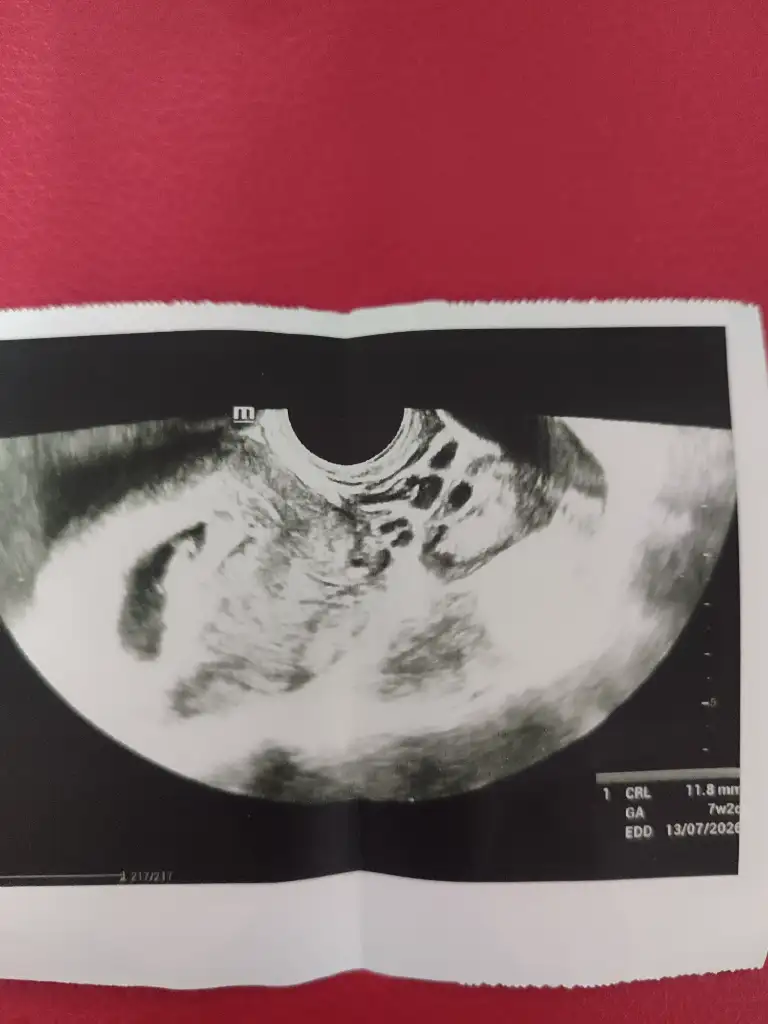

Evet usg gerçekten cok önemli benim gittiklerim devlet ve özel 2 sininde ultrasonu cok kötü 😂 verdiği görüntü beyaz bişi anlaşılmıyor bunuda bugün devlet verdi vajinal baktı karından net duyamıyorum dediği için ordan baya net dinledik kalp atısını diğer özeller de cok pahalı gerek yok 2500 vermeye dedim iyi olduğunu biliyorum ya yeter özeldekide usg kötü ama yine devletten iyiydi 2 gün önce karından duymuştuk 🤭 ilk foto devlet 2. Özel

Evet usg gerçekten cok önemli benim gittiklerim devlet ve özel 2 sininde ultrasonu cok kötü 😂 verdiği görüntü beyaz bişi anlaşılmıyor bunuda bugün devlet verdi vajinal baktı karından net duyamıyorum dediği için ordan baya net dinledik kalp atısını diğer özeller de cok pahalı gerek yok 2500 vermeye dedim iyi olduğunu biliyorum ya yeter özeldekide usg kötü ana yine devletten iyiydi 2 gün önce karından duymuştuk 🤭 ilk foto devlet 2. Özel